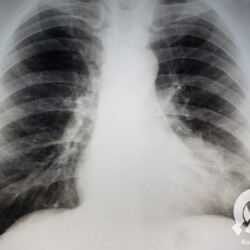

E o nome dado a esta alteração radiográfica que corresponde à substituição do ar alveolar por líquido é a consolidação alveolar.

Uma consolidação alveolar é, por definição, uma opacidade (imagem densa, branquinha) homogênea ou às vezes heterogênea (pela presença de calcificações ou cavidades), de limites mal definidos, exceto quando toca a pleura da parede ou das cissuras pulmonares. É um termo usado tanto em radiografia, como em tomografia computadorizada. Na tomografia, um outro termo é usado: vidro fosco, que é uma opacidade (branquinha mas não tanto como a consolidação), que borra o pulmão mas deixa ver os vasos de permeio (igual bigode de adolescente: dá pra ver todo o fundo).

Nós vamos mostrar aqui um pequeno apanhado de pneumonias de variados agentes, em diversos segmentos e lobos pulmonares, com extensões variadas. O objetivo é identificar o padrão radiológico de consolidação alveolar e não determinar o agente infeccioso, isso vai ser assunto para mais adiante. Aliás já antecipo que é fundamental saber localizar a lesão, porque alguns destes bichos gostam de determinados segmentos, alguns tumores também têm as suas preferências, então localização é fundamental. Se localização não fosse importante, um apartamento na beira do mar sairia o mesmo preço de um apartamento de frente pra BR-101, concordam?

Seguem alguns dos nossos casos de pneumonia para vocês treinarem os olhos e não se apavorarem nos plantões.